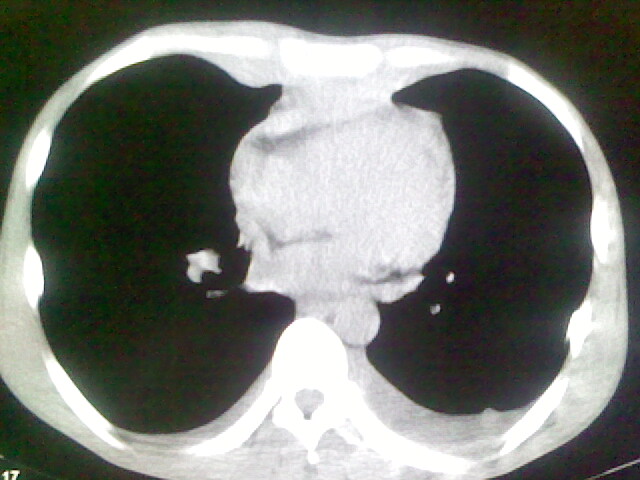

以下是引用杀毒软件在2008-9-3 6:11:00的发言:[br]侵袭性胸腺瘤------一般不侵到气管旁[br][br]考虑----纵隔淋巴瘤,心包及胸膜受累

以下是引用随光逐影在2008-9-3 7:07:00的发言:[br]1)考虑淋巴瘤可能。2)双侧胸腔积液(以左侧为甚)。3)心包积液。